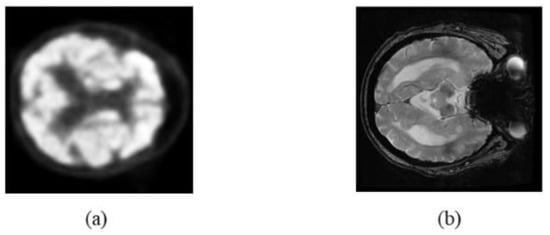

2.1. Image Data